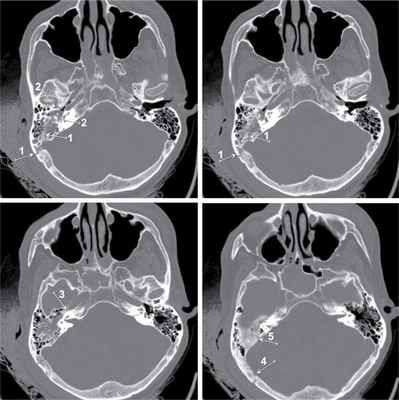

Объективное состояние больного при поступлении — кома III, шкала комы Глазго — 3 балла, пульс на сонных артериях — 40—50 уд/мин, слабого наполнения, аритмичный, АД — 80/40 мм рт.ст., мидриаз D=S, атония, арефлексия, цианоз кожи и слизистых оболочек. Доставлен в экстренную операционную, где продолжена интенсивная терапия. Проведено комплексное обследование, консультирован ЛОР-врачом, челюстно-лицевым хирургом. Выполнена фибробронхоскопия, первичная хирургическая обработка ран левого века и слизистой оболочки верхней губы. Отмечалась отогемоликворея справа, симптом «пятна» положителен. Гемодинамика на фоне вазопрессорной поддержки адреналина: пульс 90 уд/мин на сонных артериях, слабого наполнения, АД — 90/60 мм рт.ст., при увеличении показателей гемодинамики отмечалось обильное кровотечение из наружного слухового прохода, наложена асептическая повязка. Выполнена компьютерная томография головного мозга: линейный перелом каменистой части височной кости, проходящий через сигмовидный синус, канал внутренней сонной артерии, стенки наружного слухового прохода; объемного воздействия на головной мозг не выявлено, базальные цистерны не деформированы (см. рисунок). Компьютерная томограмма пирамидок височных костей больного Е. (аксиальная проекция, режим «костного окна»). Стрелками указана линия перелома, проходящая через борозду сигмовидного синуса (1), стенки наружного слухового прохода (2), канал внутренней сонной артерии (3), затылочную кость (4), верхнюю грань пирамидки височной кости (5).